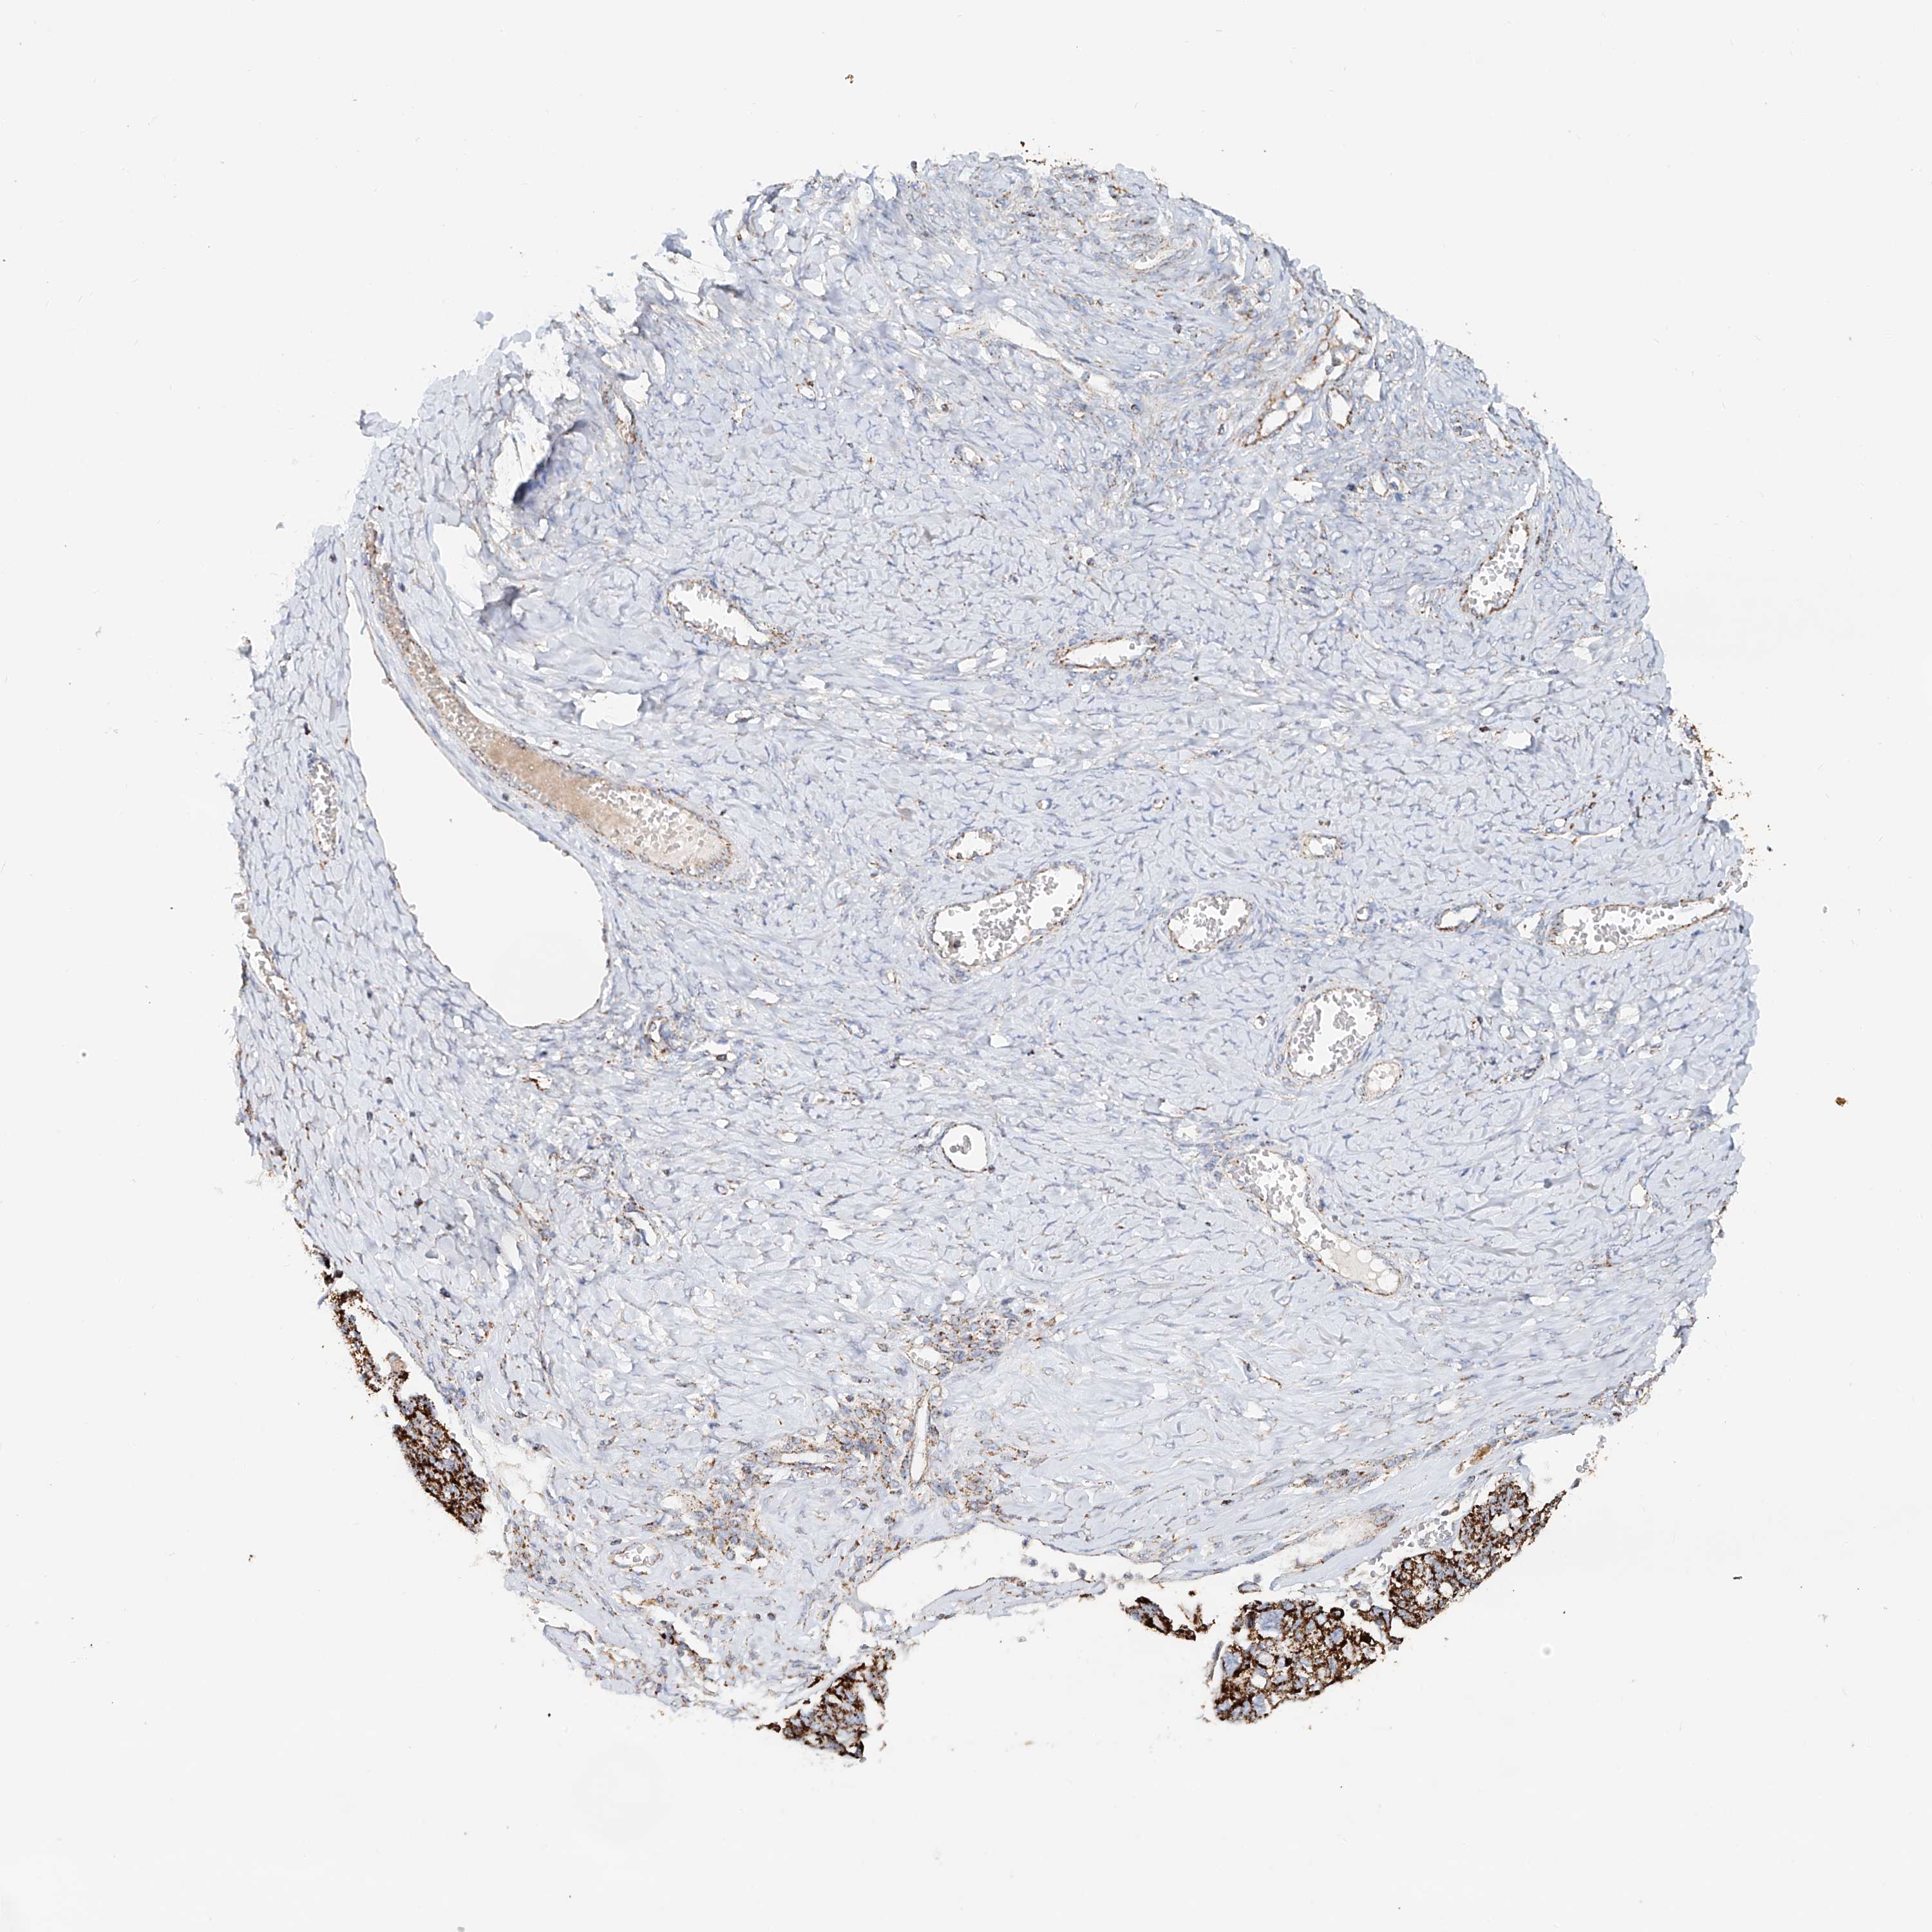

OVARIAN CANCER - Protein expressioni

A mouse-over function shows sample information and annotation data. Click on an image to view it in a full screen mode. Samples can be filtered based on level of antibody staining by selecting one or several of the following categories: high, medium, low and not detected. The assay and annotation is described here.

Note that samples used for immunohistochemistry by the Human Protein Atlas do not correspond to samples in the TCGA dataset.

Antibody stainingi

Antibody staining in the annotated cell types in the current human tissue is reported as not detected, low, medium, or high, based on conventional immunohistochemistry profiling in selected tissues. This score is based on the combination of the staining intensity and fraction of stained cells.

Each image is clickable and will lead to virtual microscopy that enables deeper exploration of all samples and also displays staining intensity scores, fraction scores and subcellular localization as well as patient and tissue information for each sample.

Antibody HPA029359

Staining

High

Medium

Low

Not detected

Intensity

Strong

Moderate

Weak

Negative

Quantity

>75%

75%-25%

<25%

None

Location

Nuclear

Cytoplasmic/membranous

Cytoplasmic/membranous,nuclear

Cystadenocarcinoma, serous, NOS

Carcinoma, endometroid

Cystadenocarcinoma, mucinous, NOS

Carcinoma, NOS